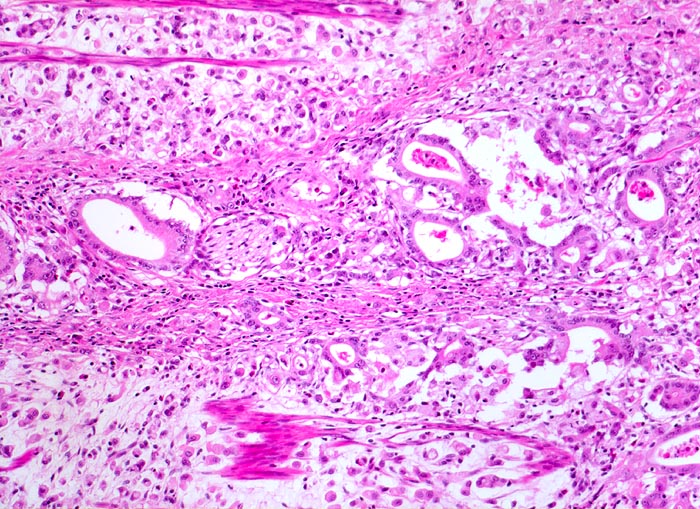

• Ein Grossteil des Tumorinfiltrats besteht aus einzeln oder in kleinen Gruppen liegenden Zellen mit intrazytoplasmatischen Schleimvakuolen, die teilweise den Kern verdrängen (Siegelringzellen): diffuser Typ des Magenkarzinoms nach Lauren.

• Nur vereinzelt Drüsenbildung.

• Lymphgefässeinbrüche.